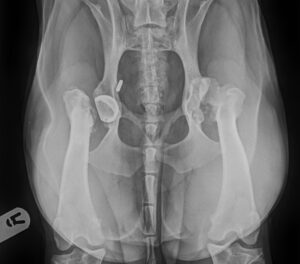

Buddy and Hip Dysplasia

Some dogs just seem to have way more than their fair share of bad

luck and Buddy is a prime example. This incredibly happy

crossbreed was only a few months old when he was diagnosed with

severe hip dysplasia affecting both hips. He had a Total Hip

Replacement performed early in 2019 but this unfortunately failed

and had to be removed. He seemed to do okay but in early 2020

following a period of forelimb lameness he was diagnosed with

bilateral Humeral Intercondylar Fissures. The elbows underwent a

protective procedure with the placement of Transcondylar Screws and again he seemed to do well until

the lameness returned due to the development of severe

osteoarthritis in the left hip and both elbows. Buddy’s management

plan wasn’t enough to keep him comfortable, so he was admitted to

the clinic in May 2023 for injection with Mesenchymal Stem Cells.

Just a few weeks later he had gone from shuffling to strutting and

has been doing well ever since! It is important to note that no intra-

articular approaches will cure or ‘fix osteoarthritis, but they can be

tremendously powerful in management of pain and improving

quality of life.

Buddy before treatment at MSK Vets